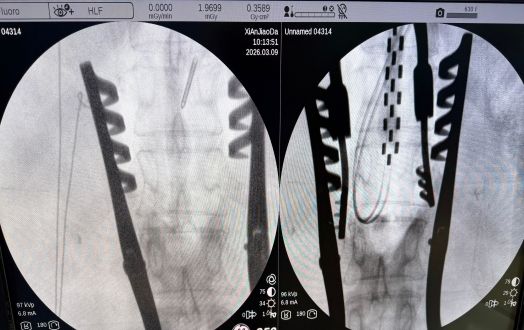

神经外科王举波副主任医师汇报了一例脊髓电刺激术治疗糖尿病痛性周围神经病患者的情况。患者是一名患糖尿病十余年的中年女性,3年前出现左侧小腿皮肤溃烂,反复换药仍难以愈合,1年前开始出现双下肢持续性疼痛并日益严重,剧痛导致夜不能寐,长期失眠,药物治疗无效,在外院接受双下肢血管介入治疗效果亦不佳,遂来我院就诊,以“糖尿病痛性周围神经病”之诊断收住院。入院时双下肢皮肤温度低,紫绀,左侧小腿皮肤溃疡直径约9cm,双下肢温度觉、触觉均减退,神经电生理检查显示“双下肢周围神经病损,感觉、运动均受累”,CTA检查见双下肢动脉广泛重度狭窄,踝肱指数极低,疼痛VAS评分达10分(VAS是一种评估疼痛强度的临床工具,将疼痛程度由轻到重计为0分﹝完全无痛﹞至10分﹝最痛﹞)。经过多学科全面细致的评估和讨论,为患者制定了以脊髓电刺激术为核心的治疗方案。术前准备充分,在麻醉科、手术室的协助下,王举波副主任医师主刀、权瑜、高攀担任助手,为患者施行硬膜外电极Ⅰ期植入术,手术顺利,术后程控测试治疗效果显著,患者疼痛迅速缓解,当日VAS评分即达到0分,遂于1周后二期手术植入永久刺激器。2周后,患者疼痛完全缓解,左侧小腿皮肤溃疡面积缩小大半,皮肤色泽改善,双下肢皮温明显回升,睡眠显著改善。

硬膜外刺激器植入术中监测及术后影像学